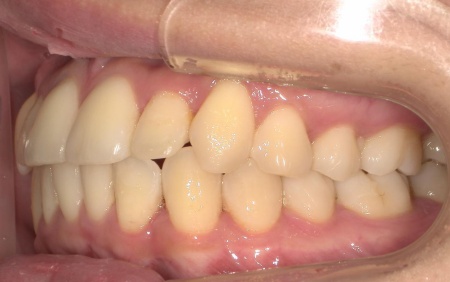

20代女性 八重歯と歯並びの乱れをマウスピース矯正装置で改善した症例

「上下の八重歯が気になる」とご相談いただきました。

拝見したところ、歯が正しく並ぶためのスペースが不足しており、歯が重なって生えてしまう叢生(そうせい)の状態が全体的に見られました。

特に上下の糸切り歯が外側にずれている、いわゆる八重歯が目立っています。